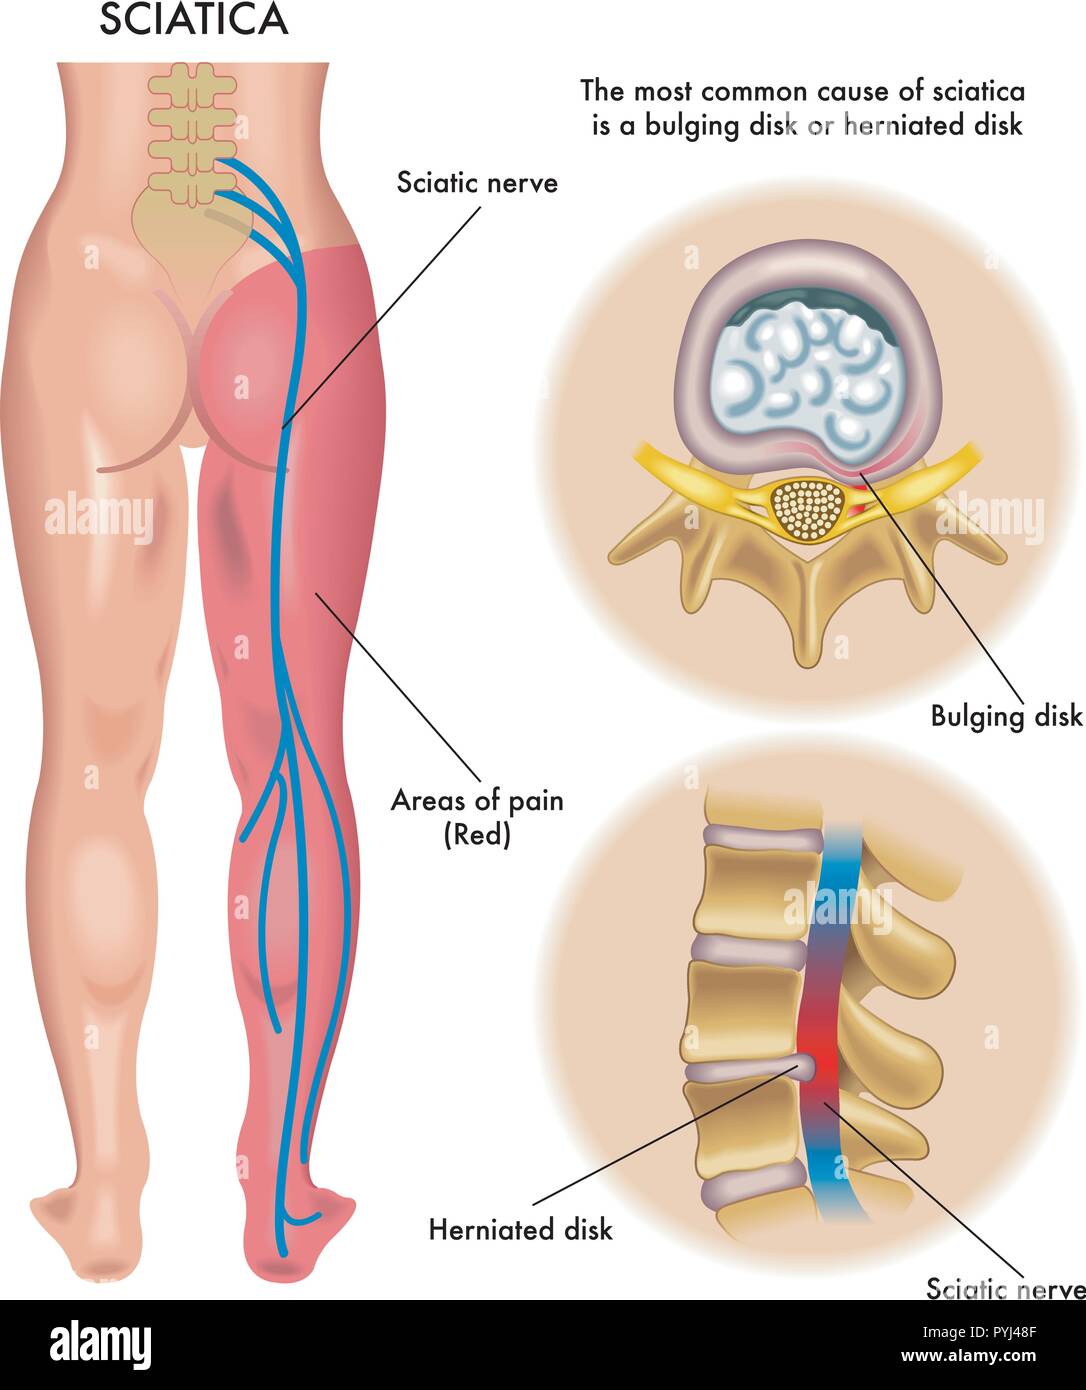

Symptômes de illustration médicale de sciatique Illustration de Vecteurhttps://www.alamyimages.fr/image-license-details/?v=1https://www.alamyimages.fr/symptomes-de-illustration-medicale-de-sciatique-image223518639.html

Symptômes de illustration médicale de sciatique Illustration de Vecteurhttps://www.alamyimages.fr/image-license-details/?v=1https://www.alamyimages.fr/symptomes-de-illustration-medicale-de-sciatique-image223518639.htmlRFPYJ48F–Symptômes de illustration médicale de sciatique